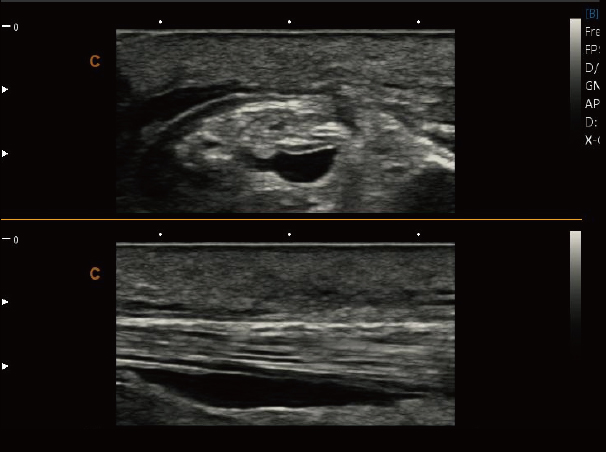

肌骨,B 模式